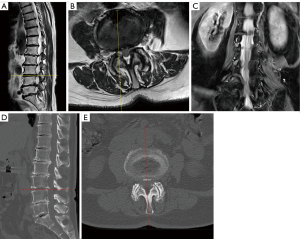

Immediately after the procedure, the patient mentioned that lower back and radicular pain in the anterior aspect of her right leg had completely disappeared. Postoperative MRI and CT revealed an expanded lumbar canal at L3–4 and decompression of the right L4 nerve root (Figure 3A-3D). The patient was discharged without any perioperative complications. No recurrence was observed for at least 3 months postoperatively. All procedures performed in this study were in accordance with the ethical standards of the institutional and/or national research committee(s) and with the Helsinki Declaration and its subsequent amendments. Written informed consent was obtained from the patient for publication of this case report and accompanying images. A copy of the written consent is available for review by the editorial office of this journal.